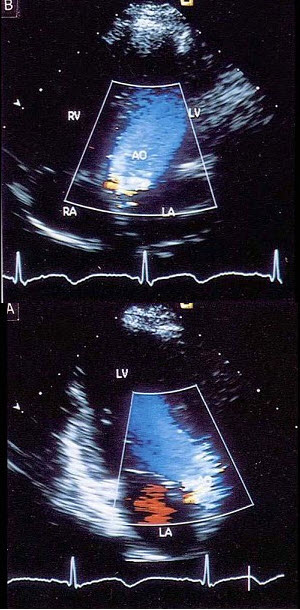

80、单项选择题

该图蓝色血流信号表示()

100、单项选择题

该病例最可能的诊断()

E.以上都不是

101、单项选择题

A.二尖瓣腱索断裂